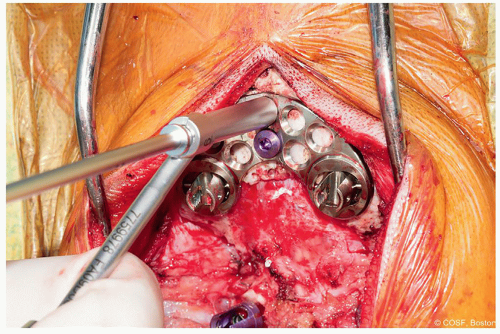

Figure 2-4 ▪ Placement of midline occipital screws through plate. Use of a stop drill may help prevent inadvertent dural penetration. (Courtesy of Children’s Orthopaedic Surgery Foundation.)

Screw fixation may be done by drilling sequentially by 2 mm with a stop drill to avoid potential overdrilling and penetrating the dura (Figure 2.4)

The majority of screws may be bicortical with tapping necessary as occipital screws have a blunt tip to avoid the dura